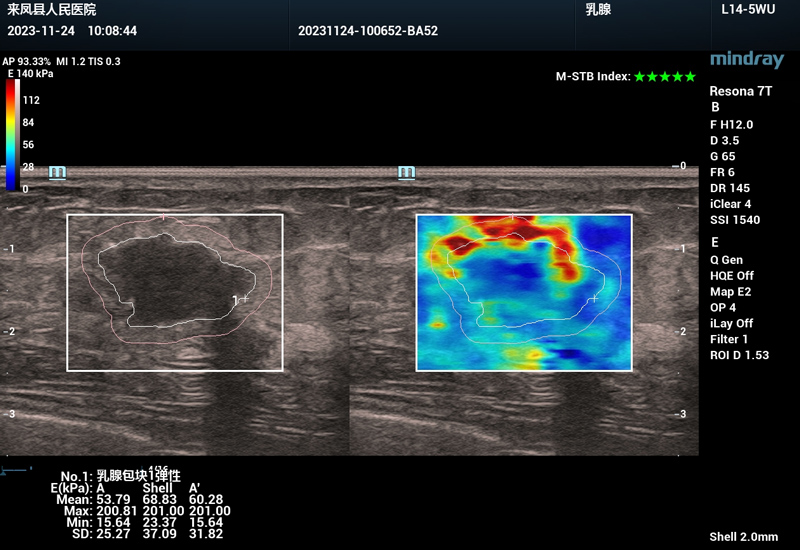

由于肿块比较可疑,来自湖北省肿瘤医院超声医学科的李芳医生帮向女士加做了弹性成像,“应变”弹性超声评分为5分,“剪切波”弹性成像提示该乳腺组织边缘硬度较高,形成了“硬环征”,综合评判该乳腺肿块BIRADS 4c类,高度怀疑乳腺癌。

特别是现在的超声弹性设备同时结合“应变”和“剪切波”两种弹性成像技术,进一步提高了诊断的可靠性。在“应变”弹性成像的基础上,再利用“剪切波”弹性成像,能进一步发现该乳腺组织边缘硬度较高,形成了“硬环征”,是恶性乳腺组织的典型病理特征之一。因此诊断提示高度怀疑乳腺癌。

乳腺组织的剪切波弹性成像图